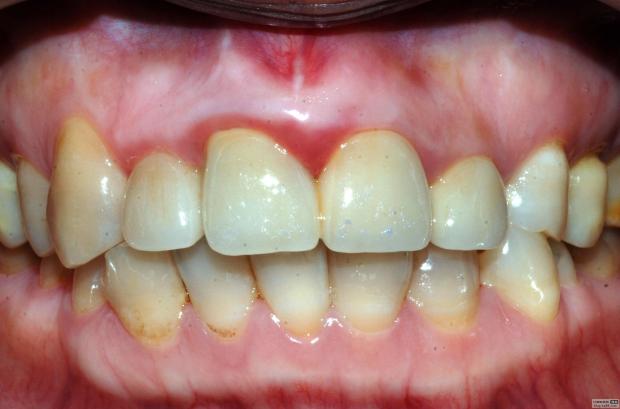

最近接到這樣一位患者,上前牙氧化鋯聯(lián)冠修復(fù)不足一年時(shí)間,現(xiàn)患者主訴左上前牙疼痛來診,檢查發(fā)現(xiàn)上前牙冷熱無反應(yīng),扣診(++),牙齦紅腫,探出血,冠邊緣不密合, X片示基牙全部已做根管治療,但是根管充填全部欠填。

先不評(píng)論修復(fù)體的顏色、形態(tài)、密合性及生物學(xué)寬度的問題,就患者而言對(duì)修復(fù)體還是比較滿意的,是因?yàn)樾迯?fù)后不久牙齒開始疼痛,吃了好多藥也不起作用才來就診檢查的,但患者剛開始不愿拆冠,經(jīng)過詳細(xì)的溝通后才同意拆冠——冠延長術(shù)——根管再治療——愈合——重新修復(fù)。可見患者雖然花了較高的費(fèi)用,但對(duì)我們醫(yī)生的要求還是很低的,但就是這么低的要求也不見得所有醫(yī)生能夠滿足患者。這個(gè)患者即使冠沒有問題,也得拆冠。患者也是牙疼才來診治的,在修復(fù)之前一定要做完善的根管治療。

病例1 由于根管充填不完善造成修復(fù)體拆除

修復(fù)后出現(xiàn)根尖周炎癥狀 根管再治療后病變愈合